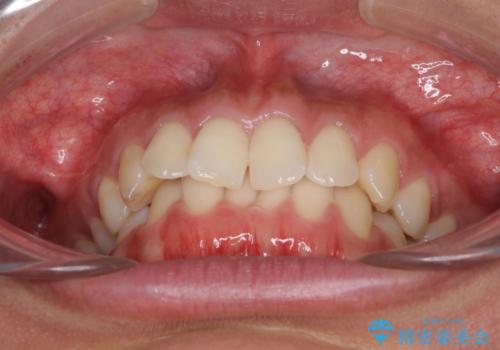

- 深い咬み合わせ(ディープバイト)と前歯のデコボコを気にして来院された患者様です。

インビザラインによる上下歯列の側方拡大と後方移動、IPR(歯と歯の間を削る)にるスペースの獲得により、デコボコとディープバイトを改善することとしました。

1日22時間の装着時間をしっかり守ってくださったので、予定通り1年で治療を終えることができました。

ディープバイトによる食いしばり癖も解消され、患者様には大変満足していただきました。